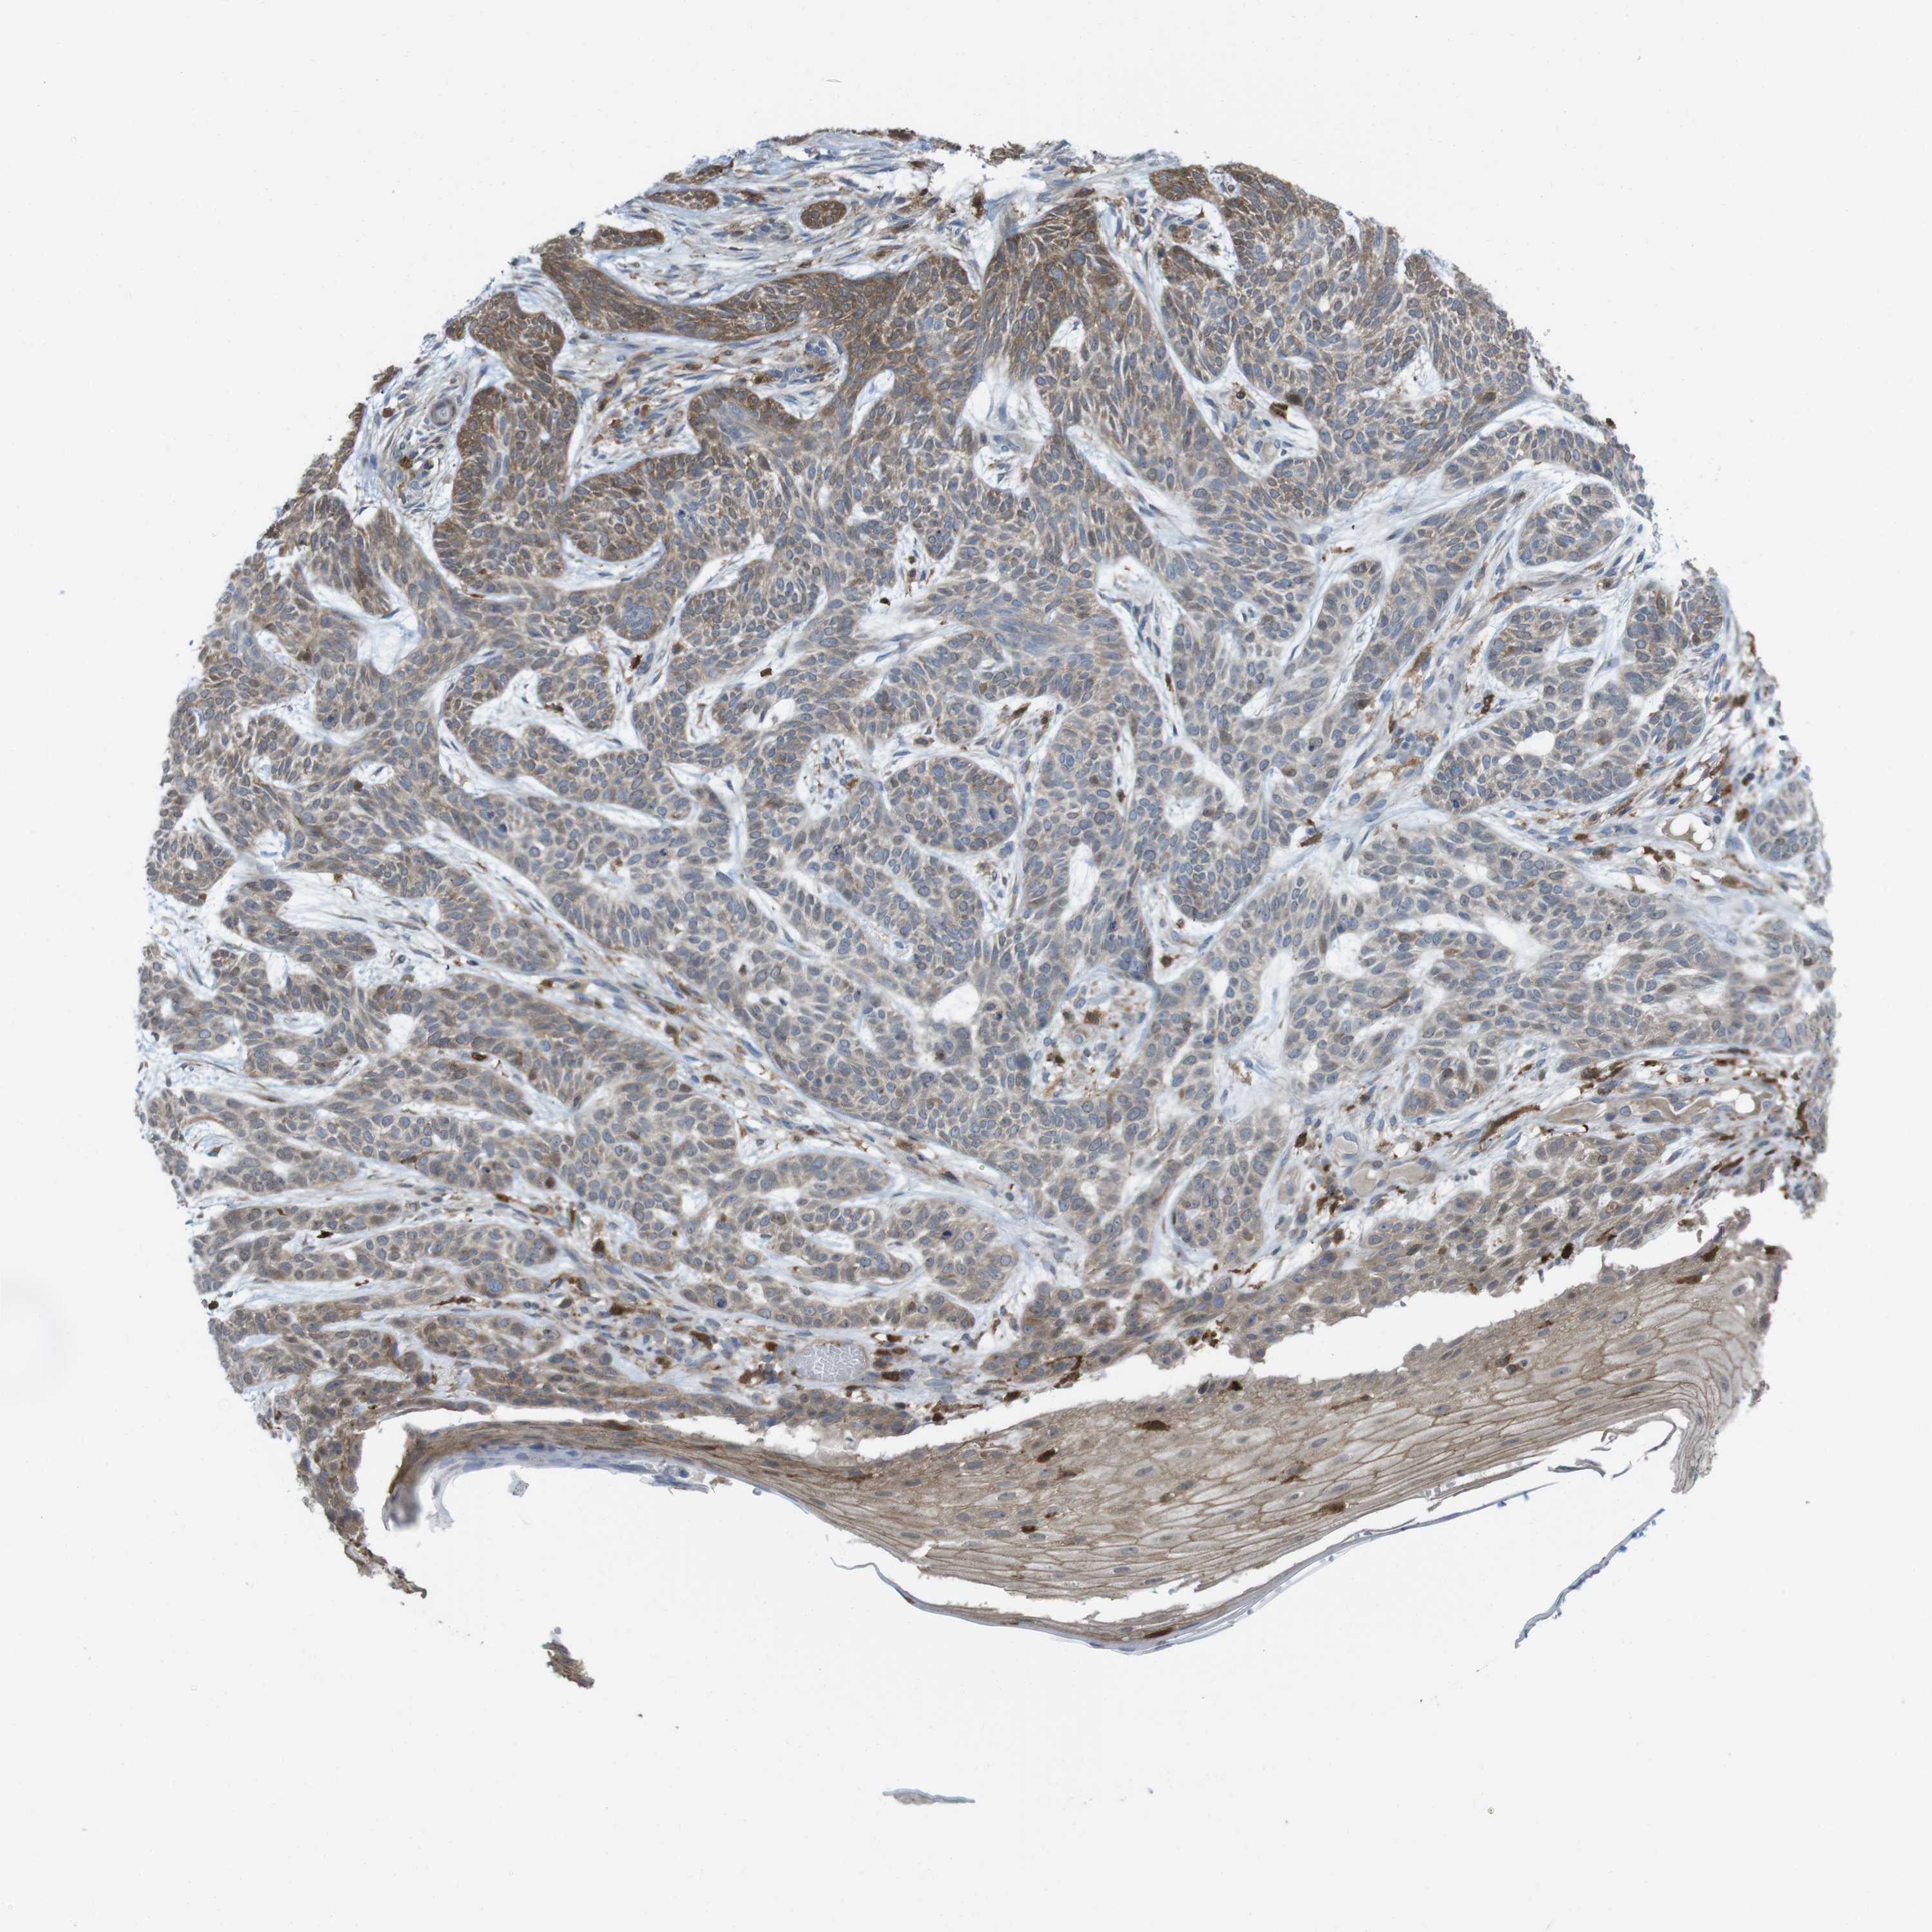

SKIN CANCER - Protein expressioni

A mouse-over function shows sample information and annotation data. Click on an image to view it in a full screen mode. Samples can be filtered based on level of antibody staining by selecting one or several of the following categories: high, medium, low and not detected. The assay and annotation is described here.

Each image is clickable and will lead to virtual microscopy that enables deeper exploration of all samples and also displays staining intensity scores, fraction scores and subcellular localization as well as patient and tissue information for each sample.

Antibody HPA001863

Staining

High

Medium

Low

Not detected

Intensity

Strong

Moderate

Weak

Negative

Quantity

>75%

75%-25%

<25%

None

Location

Nuclear

Cytoplasmic/membranous

Cytoplasmic/membranous,nuclear

Squamous cell carcinoma, NOS

Basal cell carcinoma

Squamous cell carcinoma in situ, NOS

Adnexal tumor, benign